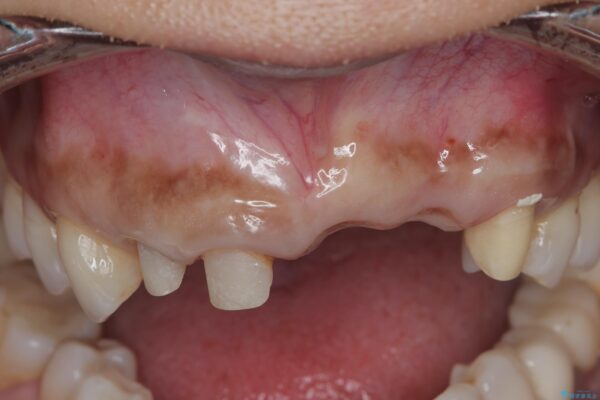

治療中

歯槽堤保存術を併用したブリッジ治療 治療中画像 歯槽堤保存術を併用したブリッジ治療 治療中画像 歯槽堤保存術を併用したブリッジ治療 治療中画像 歯槽堤保存術を併用したブリッジ治療 治療中画像 歯槽堤保存術を併用したブリッジ治療 治療中画像 歯槽堤保存術を併用したブリッジ治療 治療中画像 歯槽堤保存術を併用したブリッジ治療 治療中画像

一見して問題ないように見える左側の2前歯は、セラミックを除去してみると亀裂や虫歯の再発が見られました。

抜歯時に可及的に歯肉のボリュームを保つよう骨充填材とコラーゲン製剤による填塞を行い審美的かつ機能的なブリッジとなるよう治療を進めます。